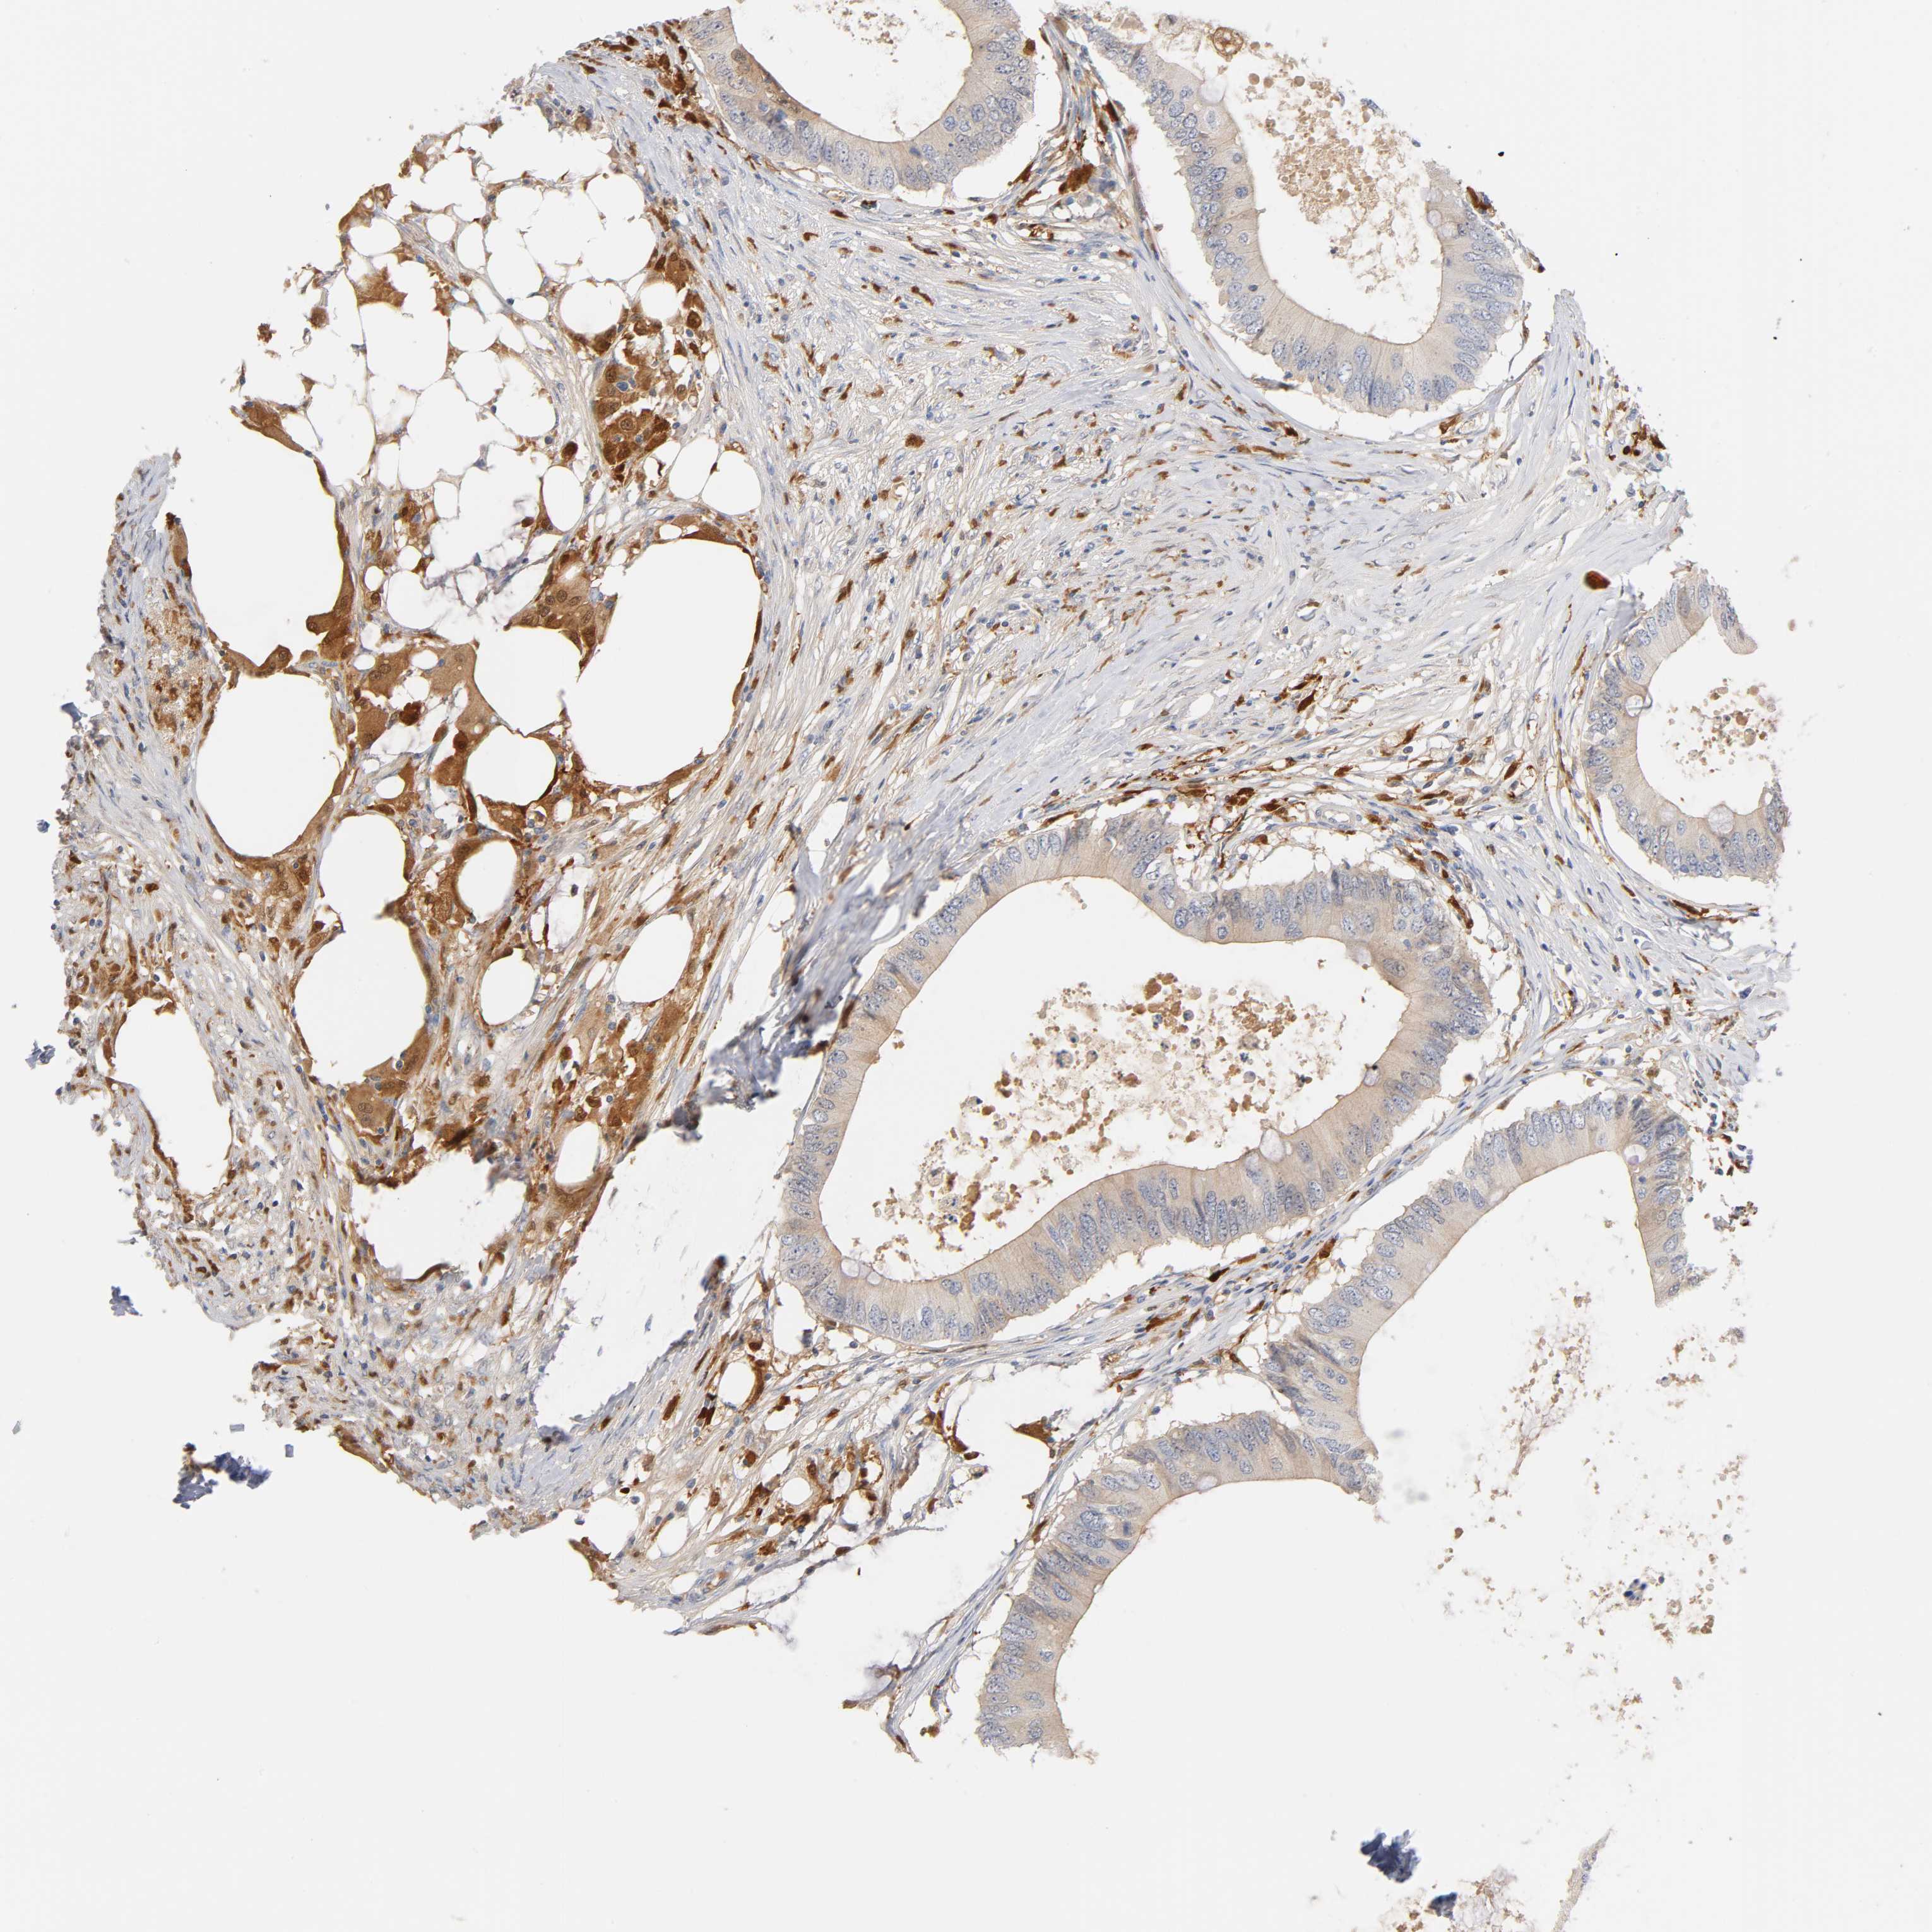

CANCER COLORECTAL CANCER Show tissue menu

Colorectal cancer

Human cancer